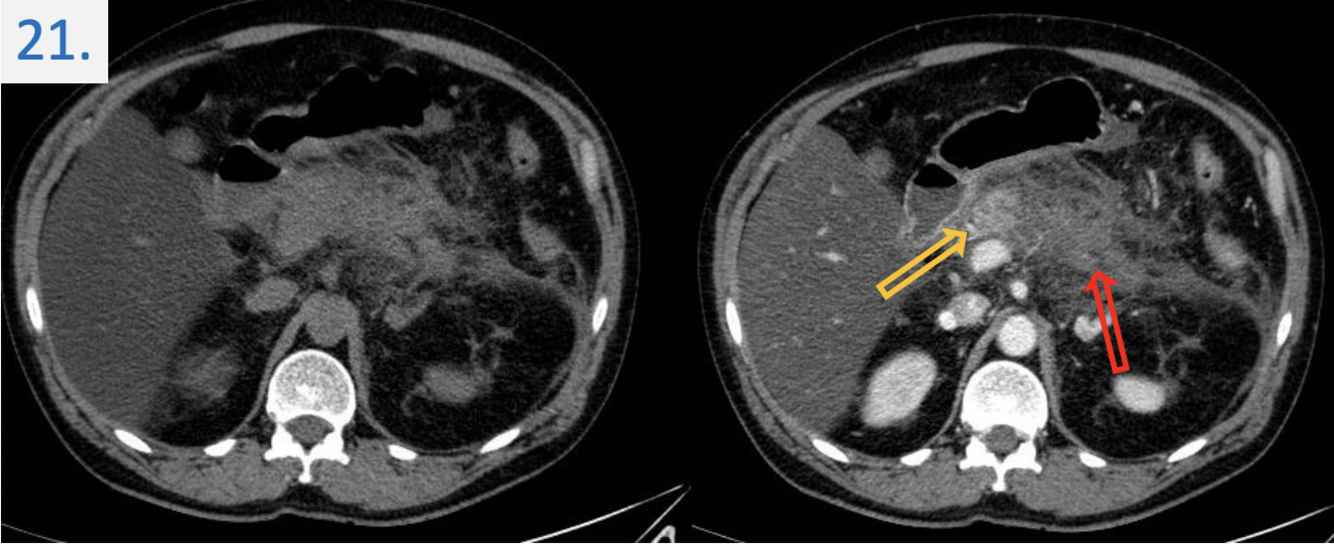

21